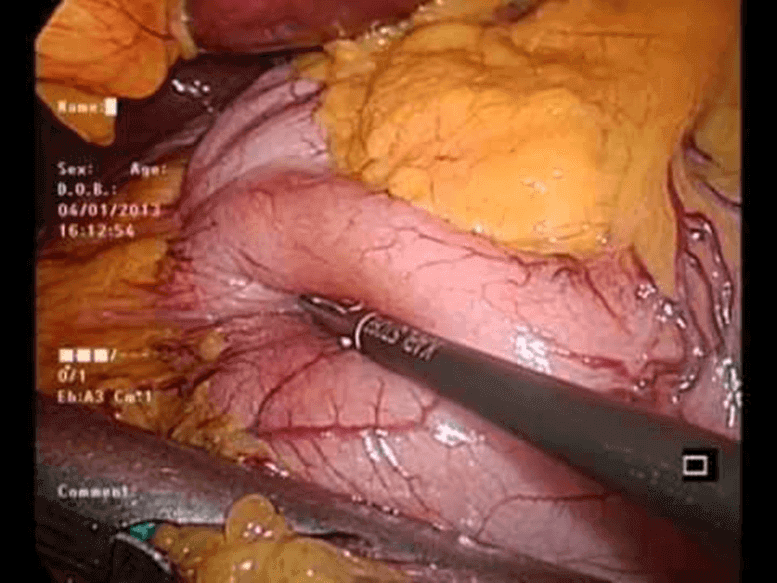

Mide küçültme ameliyatı nasıl oluyor? Son zamanlarda çok konu olan ve merak edilen obezite tedavisinde en çok uygulanan yöntem tüp mide ameliyatıdır. Hem ülkemizde hemde dünyada uygulanan bu ameliyat yöntemi nasıl oluyor?